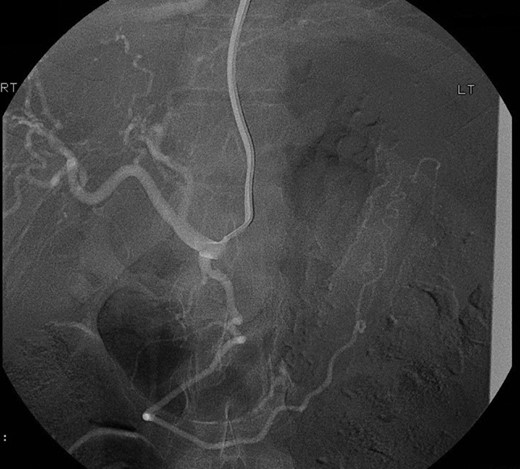

Selective angiogram using the Seldinger technique via left brachial approach to visualize the celiac trunk and superior mesenteric artery branches failed to show the pseudoaneurysm leading to the conclusion that possibly it had a different origin not accessible by angiography (Fig. 2).

Selective angiogram of the celiac trunk failing to demonstrate the pseudoaneurysm.